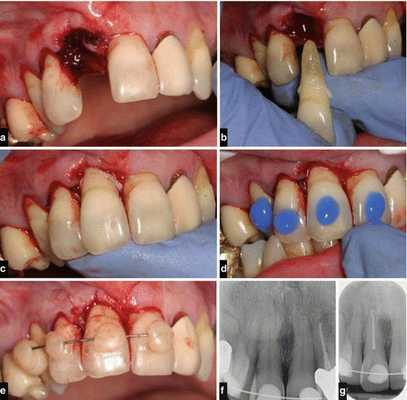

Тактика врача при переломе корня определяется характером и локализацией повреждения, возрастом пациента, уровнем смещения фрагментов. При выявлении поперечного перелома апикальной трети с нарушением витальности пульпы проводят экстирпацию коронковой и корневой пульпы, медикаментозную и механическую обработку каналов с последующим их пломбированием временной кальцийсодержащей пастой. После обтурации корневых каналов методом латеральной или вертикальной конденсации гуттаперчи производят хирургическое вмешательство, цель которого при переломе корня зуба заключается в удалении отломанного апикального фрагмента. При сохранении витальности пульпы показана иммобилизация зуба специальной каппой или проволочной шиной, зафиксированной к 2 интактным зубам по обе стороны от поврежденного с помощью жидкого фотополимерного материала.

Если при поперечно-срединном переломе корня необратимых изменений в пульпе не наблюдается, чтобы обеспечить необходимые условия для сращения фрагментов, применяют каппу, стекловолоконную или проволочно-композитную шины. В случае выявления признаков нежизнеспособности пульпы терапия перелома корня зуба включает этап эндодонтического лечения, установку штифта с репозицией, фиксацией, иммобилизацией отломков. При вертикальном или косом переломе однокорневые зубы подлежат удалению. В случае разлома одного из корней моляров или премоляров выполняют зубосохраняющие операции. При гемисекции зуба через жевательную поверхность по бифуркации в щечно-оральном направлении бором разрезают коронку. Поврежденный корень удаляют. Сохранившийся здоровый корень используют в качестве опоры при протезировании. Выявление разлома корня временного зуба является прямым показанием к его удалению.